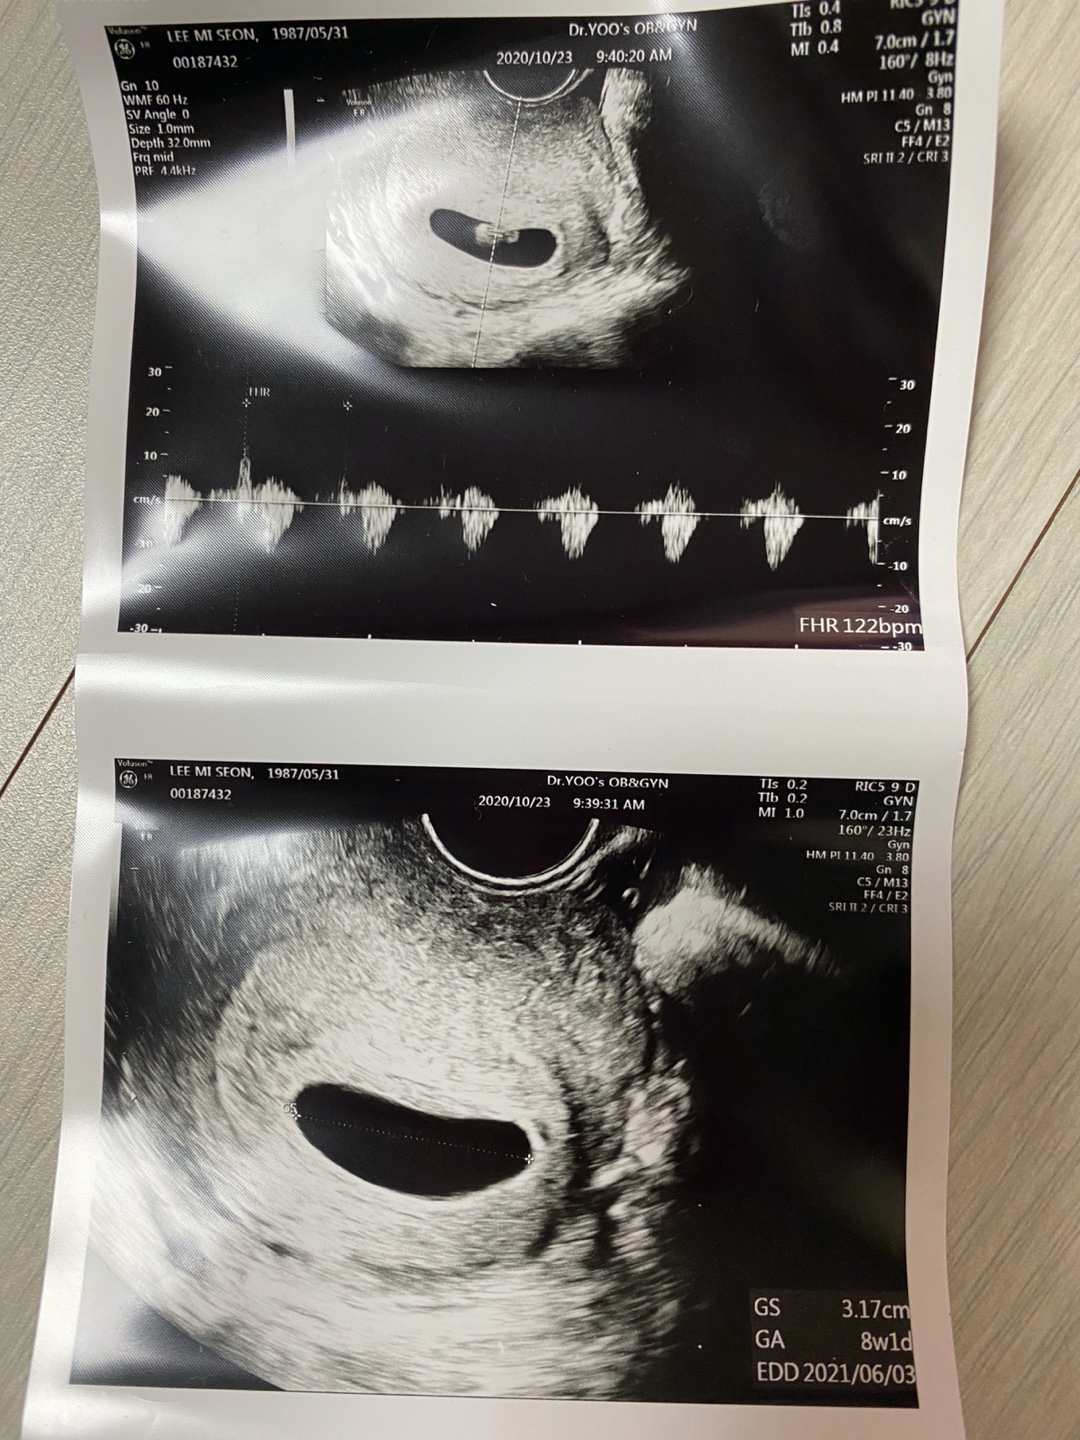

뒤이어 초음파를 보는데 아기집은 더 커져있었고 집만 있었던 공간에는 1cm도 안되는 6주차 작은 아기가 있었고 난황도 있었다.

바로 반짝반짝하는 심장을 확인하고 심장소리까지 들었다.

선생님은 6주4일 날짜를 확인해주시고 내년 6월14일 예정일과

주수에 맞춰 아기집도 아기 크기도, 심장 소리도 좋다고 했다.